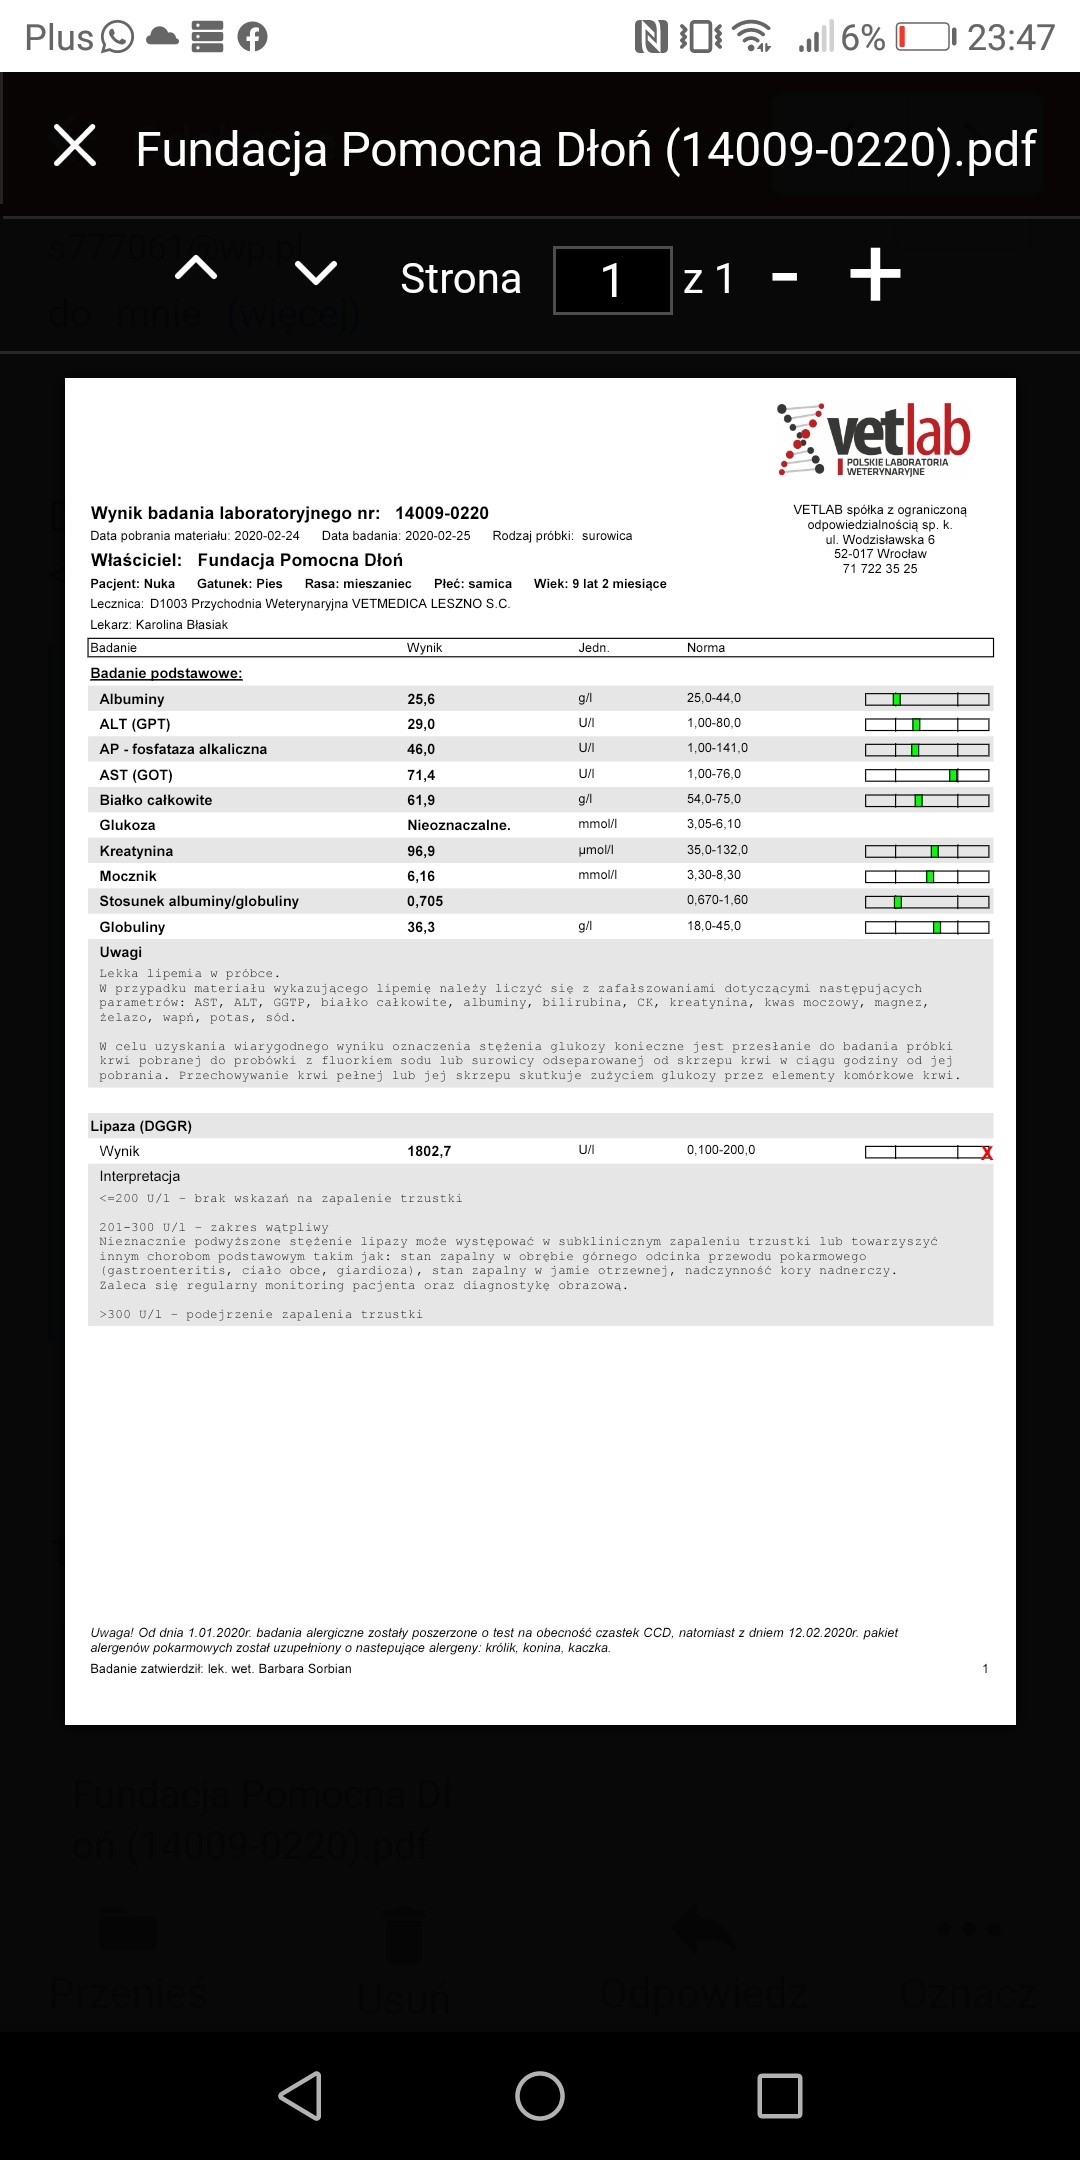

Kochani ta zbiórka jest założona na utrzymanie i leczenie suni Nuki zabranej z fatalnego przytuliska do hotelu by nie trafiła do schroniska. W hotelu przebywa już prawie 4 lata. Jest już starsza sunia... Takie psiaki maja małe szanse na adopcję. Dodatków problemem Nuki było nieakceptowanie małych dzieci. Nie mogliśmy jednak pozwolić by zginęła w schronisku. Czas nie oszczędza jednak Nuki i poglebily się problemy zwyrodnieniowe oraz doszło zapalenie trzustki. Nuka by żyć bez bólu musi dostawać lek o nazwie cimaglex 80 mg. Miesięczny koszt leczenia to 200 zł. Do tego musi jeść karmę niskotłuszczowa dla trzustkowcow. Koszt karmy takiej weterynaryjnej to ok. 250 zł.